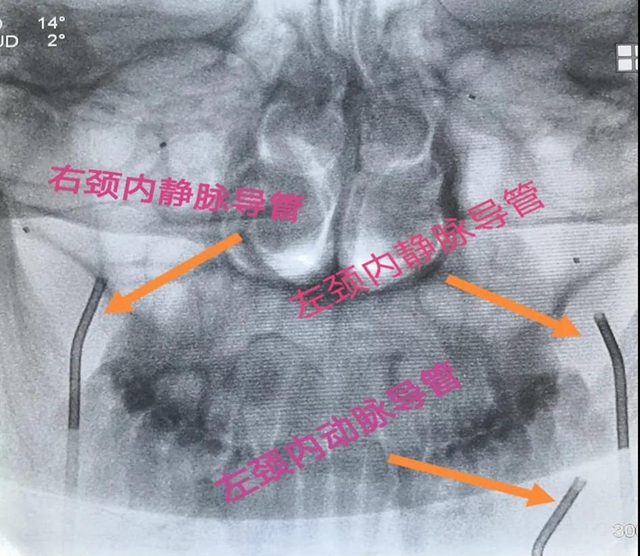

经过内分泌与代谢内科、神经外科、核医学科的多学科讨论,决定由介入医学部副主任黄昌仁教授、神经外科彭汤明博士和内分泌与代谢内科白雪主治医师开展双侧岩下窦静脉采血技术,通过对病灶经行定位,从而为患者能否进行垂体手术提供依据。

“这项技术需要采血的脑部血管非常细微,对神经介入技术要求很高,但此处采血,最能反应病人实际水平,对定位定性诊断和精准治疗有非常高的临床价值。”黄昌仁教授表示,通过多学科合作完成的这项技术,填补了神经外科神经介入的一项空白,更是多学科联合诊疗的成功范例。